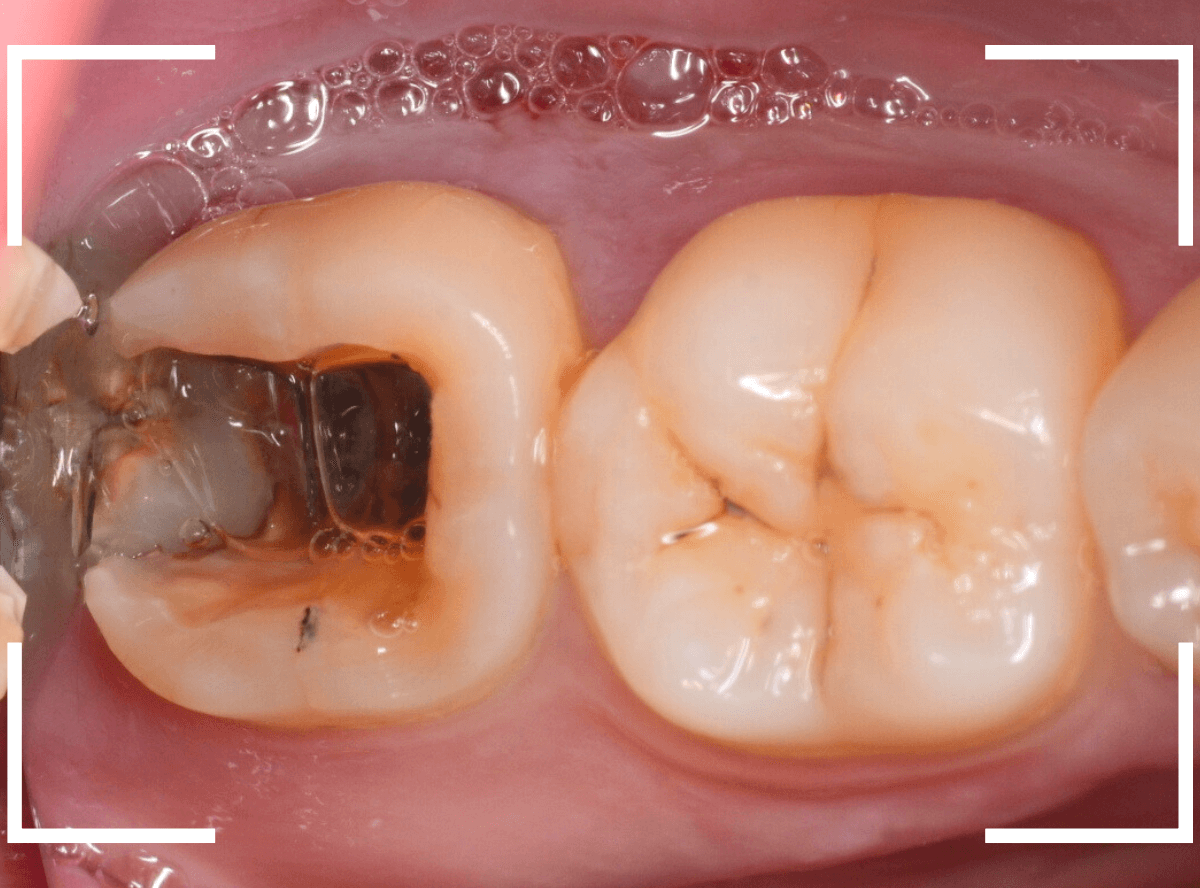

お口の中を確認すると、上の奥歯がひどい虫歯です。

その奥のおやしらずは歯の残骸が残っている状態です。

手前の歯も、大量の歯石がついています。

今回は、痛みもなく、見た目にはまだ治療で何とかなりそうに見えるケースです。

大きな虫歯なのはわかりますが、治療で何とかなりそうにも見えます。